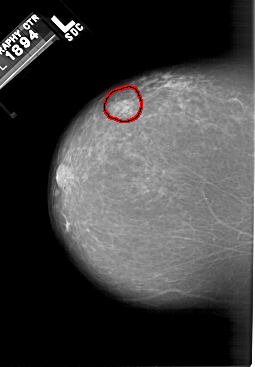

A_1498_1.LEFT_MLO

FILE: A_1498_1.LEFT_MLO.OVERLAY

TOTAL_ABNORMALITIES 1

ABNORMALITY 1

LESION_TYPE MASS SHAPE OVAL MARGINS OBSCURED

ASSESSMENT 4

SUBTLETY 4

PATHOLOGY BENIGN

TOTAL_OUTLINES 1

BOUNDARY